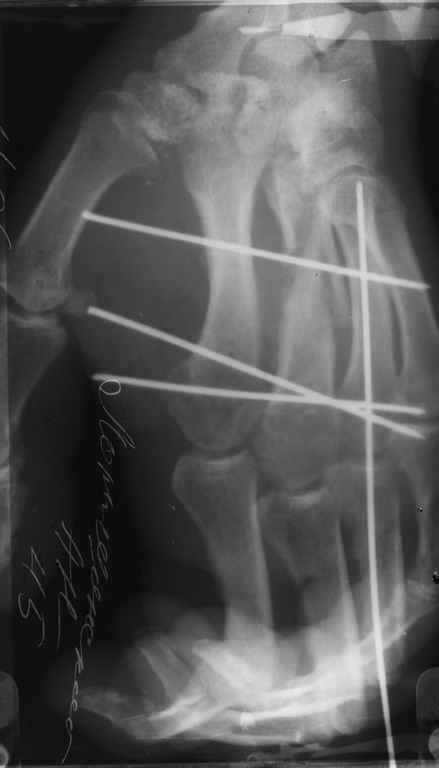

Диагноз на 15.07.05: Стойкая смешанная дермотеногенная контрактура 3,4 пальца правой кисти 3 степени.

-- удалить спицы;

-- сделать рентгенограмму;

Диагноз: Стойкая Смешанная дермотеногенная контрактура 3,4 пальца правой кисти.

Судя по выписному эпикризу, рентгенограммам и фотографиям, пациенту

показано этапное лечение.

Зачем спица в 4 Пястной кости?